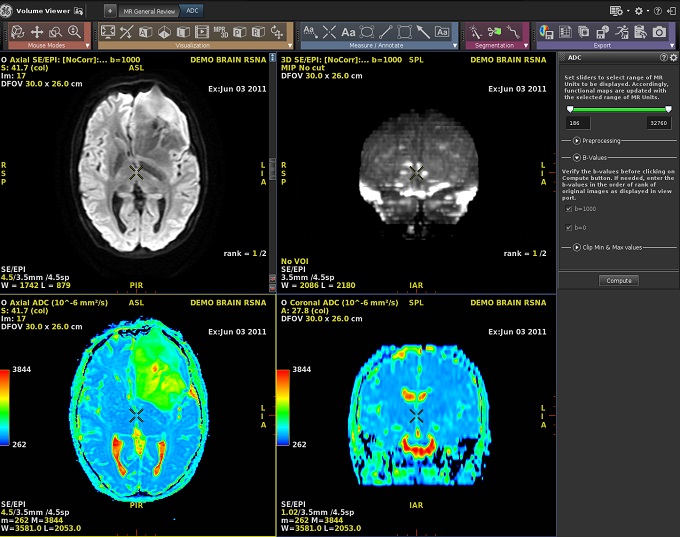

- In this example, a multi-phase series is in the primary viewport and Brainstat AIF is selected from the

Figure 2. Select a protocol from the list

Figure 3. In this example, ADC is launched